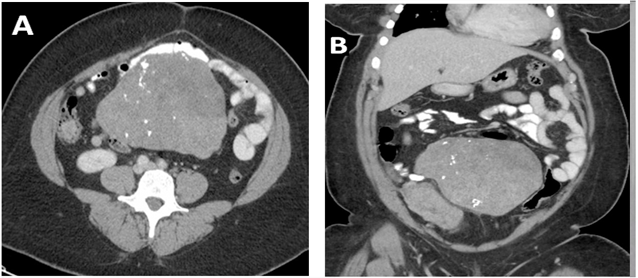

Restrictive lung diseases (RLD) are defined by reduced lung volumes, which are demonstrated on pulmonary function testing: FEV1/FVC ≥0.70 and baseline FVC <80% predicted [10]. RLD are categorized into intrinsic lung diseases due to alterations in lung parenchyma, idiopathic fibrotic disorders, and extrinsic lung diseases due to issues with the chest wall, pleura, or neuromuscular apparatus [10, 11]. There are numerous factors that can lead to restrictive lung function including older age, medication use, family history, occupational/environmental history, smoking status, higher BMI and presence of diabetes [12]. The patient did not have any significant risk factor except for her body mass index 32.9 kg/m2 [13]. It is reasonable to postulate a contributory role of her overall body habitus, but certainly not the primary factor based on the severity of her RLD. Another possible explanation is a mass effect from the large primary uterine neoplasm causing decreased lung volumes. CT of the abdomen and pelvis in our patient showed multiple large uterine masses with calcifications measuring up to 17 cm in diameter Figure 2.

Figure-2. CT of the abdomen and pelvis with contrast. A) Multiple large uterine and exophytic uterine masses with calcifications. B) The largest mass creates a mass effect in the abdomen on the bowel.

Source: Patient.